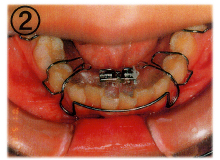

当医院では「床(しょう)矯正」という矯正治療を実践しております。

基本的には永久歯を抜かず、顎を拡げて歯を並べる治療の事です。

床矯正で使用する装置は簡単に取り外せるので、虫歯や歯周病を患いにくく、清潔な口腔環境が保てます。